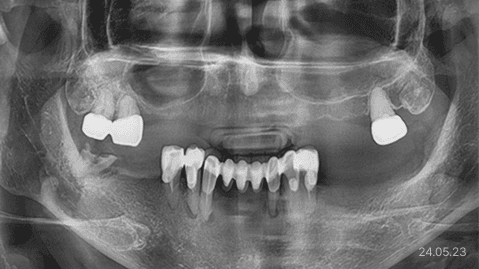

상악동 거상술 · 무절개 임플란트

상악동 거상술 ·

무절개 임플란트

상악동 격벽 · 매우 얇은 잔존뼈

*위 사진은 환자 본인 동의를 얻어 동일 조건에서 촬영 되었습니다. 모든 치료에는 부작용이 발생할 수가 있습니다.